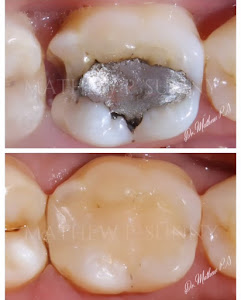

Welcome to our gallery

See how our company transforms ideas into reality. This gallery is a visual testament to our work and achievements.